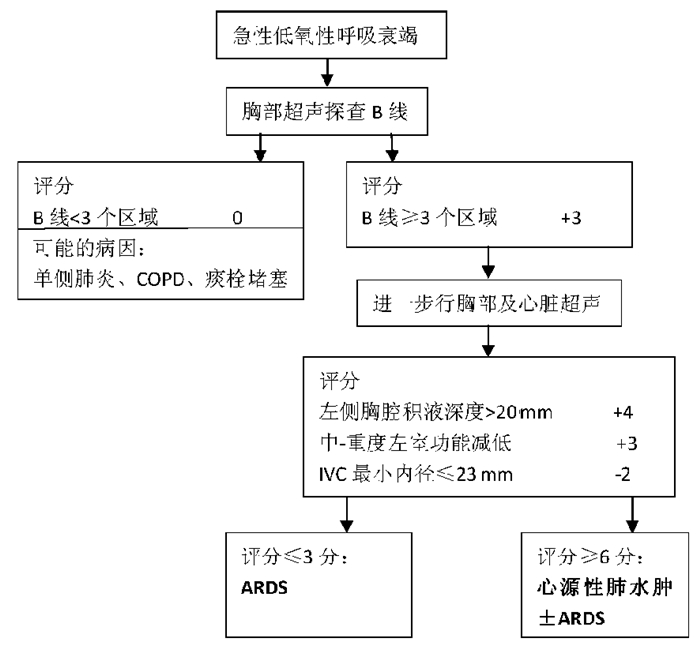

(3)CCUS流程[23]:2015年,用于早期诊断急性低氧性呼吸衰竭的CCUS(critical care ultrasonography)超声诊断流程发表于Chest杂志,该草案主要评估B线区域、胸腔无回声区、左心功能及下腔静脉状态(图 33)。根据综合表现判断引起急性低氧性呼吸衰竭的常见病因如肺炎、ARDS、心源性肺水肿等。

| 图 33 用于早期诊断急性低氧性呼吸衰竭的CCUS超声诊断流程 |